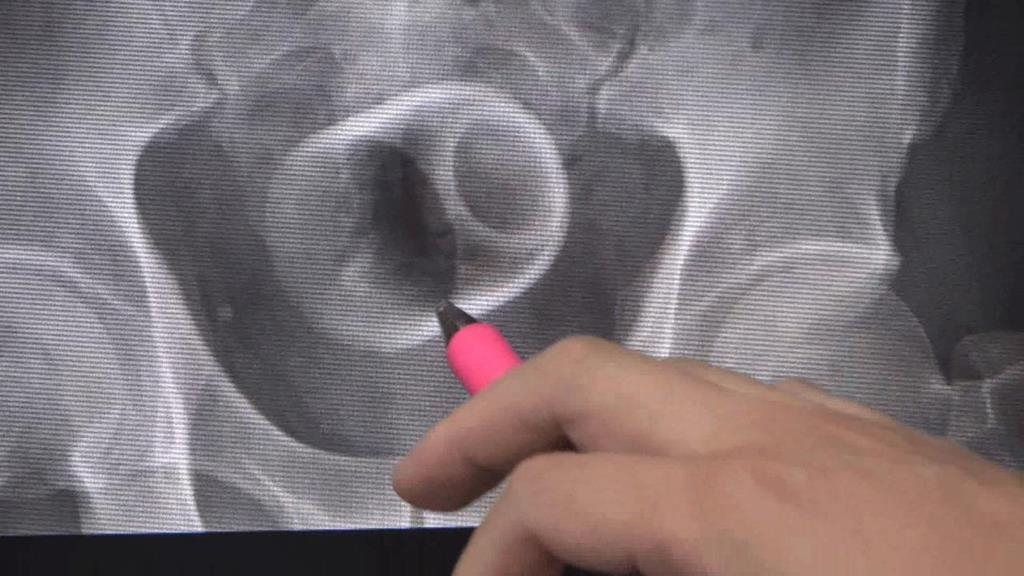

中部中心/陳仕承、陳建華報導台中市一名男子,超過三天無法解便肚痛難耐,到醫院求診,沒想到,X光檢查後竟發現,男子骨盆腔內,有一個喝茶用的陶瓷杯,讓醫師十分驚訝!由於杯子光滑難以用器械取出,最後只好開刀,同時做了一個人工造口,讓患者能夠暫時解便。

台中市一名男子,超過三天無法解便肚痛難耐,到醫院求診,沒想到,X光檢查後竟發現,男子骨盆腔內,有一個喝茶用的陶瓷杯,讓醫師十分驚訝!由於杯子光滑難以用器械取出,最後只好開刀,同時做了一個人工造口,讓患者能夠暫時解便。

綠茶甘醇入喉,但拿來品茶的瓷杯,怎麼莫名其妙,出現在男子的骨盆腔內。X光攝影一照,杯子清晰可見,連看診的醫師,都感到十分詫異。

原來,台中市這名男子,腹脹超過三天無法解便,肚子痛到受不了,不得已到醫院求診,但他起先害羞不提及自己肛門塞了一個杯子,最後在X光檢查之下才被發現,不過由於杯緣光滑,無法使用器械取出,加上杯子全被大腸包住,部分腸子缺血造成壞死,最後只好全身麻醉,開腸破肚取出杯子。醫師表示,肛門塞進異物,臨床上是基於好奇或想要尋求刺激,提醒此舉可能造成肛門括約肌鬆弛失禁,甚至讓腸子壞死破裂,嚴重的話,會引發腹腔感染,併發腹膜炎,甚至有致死危機。